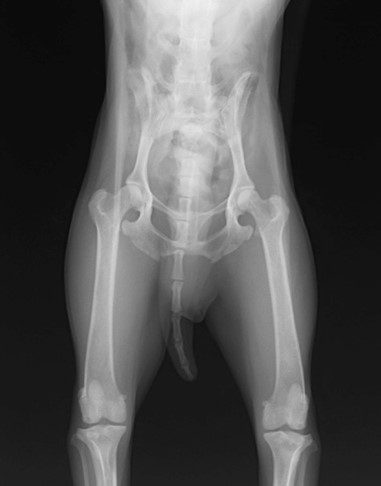

眼球摘出、眼瞼腫瘤切除、チェリーアイ整復、眼瞼縫合、瞬膜フラップ、眼球突出整復、耳介切除、垂直耳道切除、総耳道切除、鼻鏡切除、口腔腫瘍切除(上顎骨切除、下顎骨切除を含む)、各種抜歯(猫の全臼歯抜歯含む)舌腫瘍切除、唾液腺嚢胞切除、皮膚腫瘤切除、断脚(前肢、後肢、片側骨盤切除)、断尾、肺葉切除、胸腺腫切除、心膜切除、横隔膜ヘルニア整復、肝臓腫瘍切除、胆嚢摘出、胃切開、胃拡張胃捻転症候群整復、胃腫瘍切除、腸管切開、腸管腫瘍切除、直腸腫瘍切除(粘膜、全層プルスルーなど)、腎臓摘出、SUB設置手術、脾臓摘出、副腎摘出、膀胱切開、膀胱腫瘍切除(部分切除、全摘出、膀胱尿道一括切除など)、卵巣腫瘍切除、精巣腫瘍切除、卵巣子宮全摘出、肛門嚢切除、各種骨折、膝蓋骨脱臼整復、股関節脱臼整復、大腿骨頭切除、椎間板ヘルニア(各種椎弓切除術)、各種リンパ節切除 など